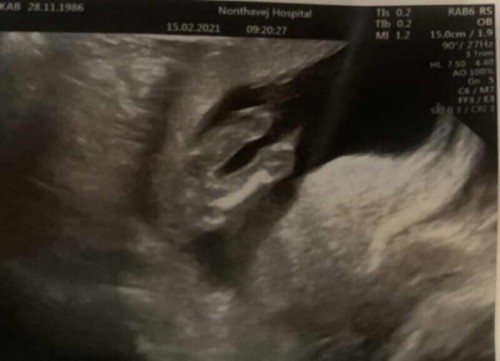

คุณหมอเดาว่าหนูเพศ หญิง ค่ะ🤰🏻👧🏻😁 ซาวด์ตอน15w6d คุณแม่ทีมสิงหารู้เพศกันหรือยังค่ะ😊 #ตอนนี้19w2dแล้วค่ะ😁 #ท้องแรก